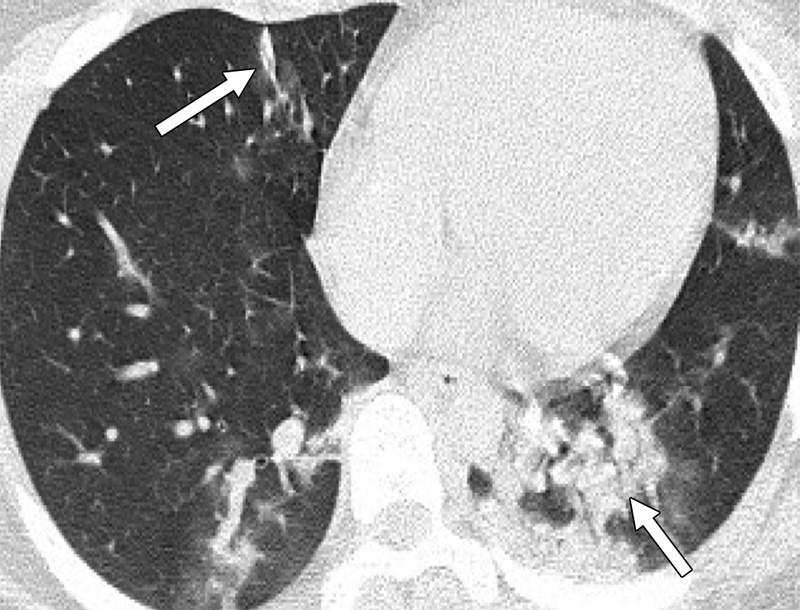

Μία εικόνα χίλιες λέξεις. Αξονικές τομογραφίες νέων κάτω από 18 έτη με Covid-19 (18 ετών, 15 ετών, 14 ετών και 8 ετών). Κανένας ασθενής δεν είχε υποκείμενα νοσήματα ή ανοσοκαταστολή. Οι ασθενείς δεν χρειάστηκαν συμπληρωματικό οξυγόνο, διασωλήνωση ή ΜΕΘ. Πρόκειται για απλά-κοινά περιστατικά Covid-19.

Ωστόσο έχουν πολύ “εντυπωσιακές” βλάβες και είναι άγνωστο τι θα προκαλέσουν αυτές οι βλάβες σε βάθος χρόνου. Για την πλειονότητα του κόσμου το ερώτημα είναι απλό: Θέλουν να υποβάλουν τους πνεύμονές τους σε αυτές τις βλάβες για να δουν αν αντέχουν; Και αν αντέξουν την πρόκληση (όπως προβλέπεται ότι θα αντέξουν οι περισσότεροι νέοι) θέλουν να δουν πόσα χρόνια ή αντοχές έχασαν στην πορεία; Με το εμβόλιο προστατεύουμε τους πνεύμονές μας από βαρύτατη καταπόνηση!